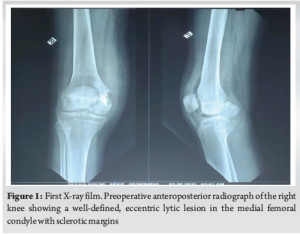

A 15-year-old girl presented with a 6-month history of right knee discomfort, which progressively worsened over time. The pain was insidious in onset and was notably aggravated by weight-bearing activities and sitting cross-legged. Although initially intermittent and relieved by analgesics, the discomfort gradually increased in intensity, interfering with her daily activities. She noticed a swelling over the medial aspect of her right knee. The swelling was progressive and unrelated to redness, warmth, or systemic symptoms such as fever, weight loss, or appetite changes. She denied any history of trauma, previous similar complaints, or swelling in other areas. Interestingly, she reported experiencing nocturnal pain – a characteristic symptom of bone tumors – but no variation in discomfort during the day. On local examination, an irregular, poorly defined swelling was palpated 4 cm medial to the patella. The overlying skin appeared normal, with no signs of discoloration or ulceration. Further examination revealed tenderness over the medial tibial and femoral condyles. The swelling was firm, immobile, and seemed closely associated with the underlying bone. Mild suprapatellar fullness was noted. There was no joint crepitus, and the knee maintained a full range of motion from 0 to 130°. The patient’s gait was normal, and there was no limb length discrepancy. Growth plate involvement was not quantified using growth scanograms, which would be useful to monitor for potential physeal arrest or future limb length discrepancy. Radiographs showed a well-demarcated lesion in the medial femoral condyle on the anteroposterior view. MRI and CT confirmed a lesion in the medial femoral condyle. Chondroblastoma was suspected in view of the calcification of the matrix. (Fig. 1).